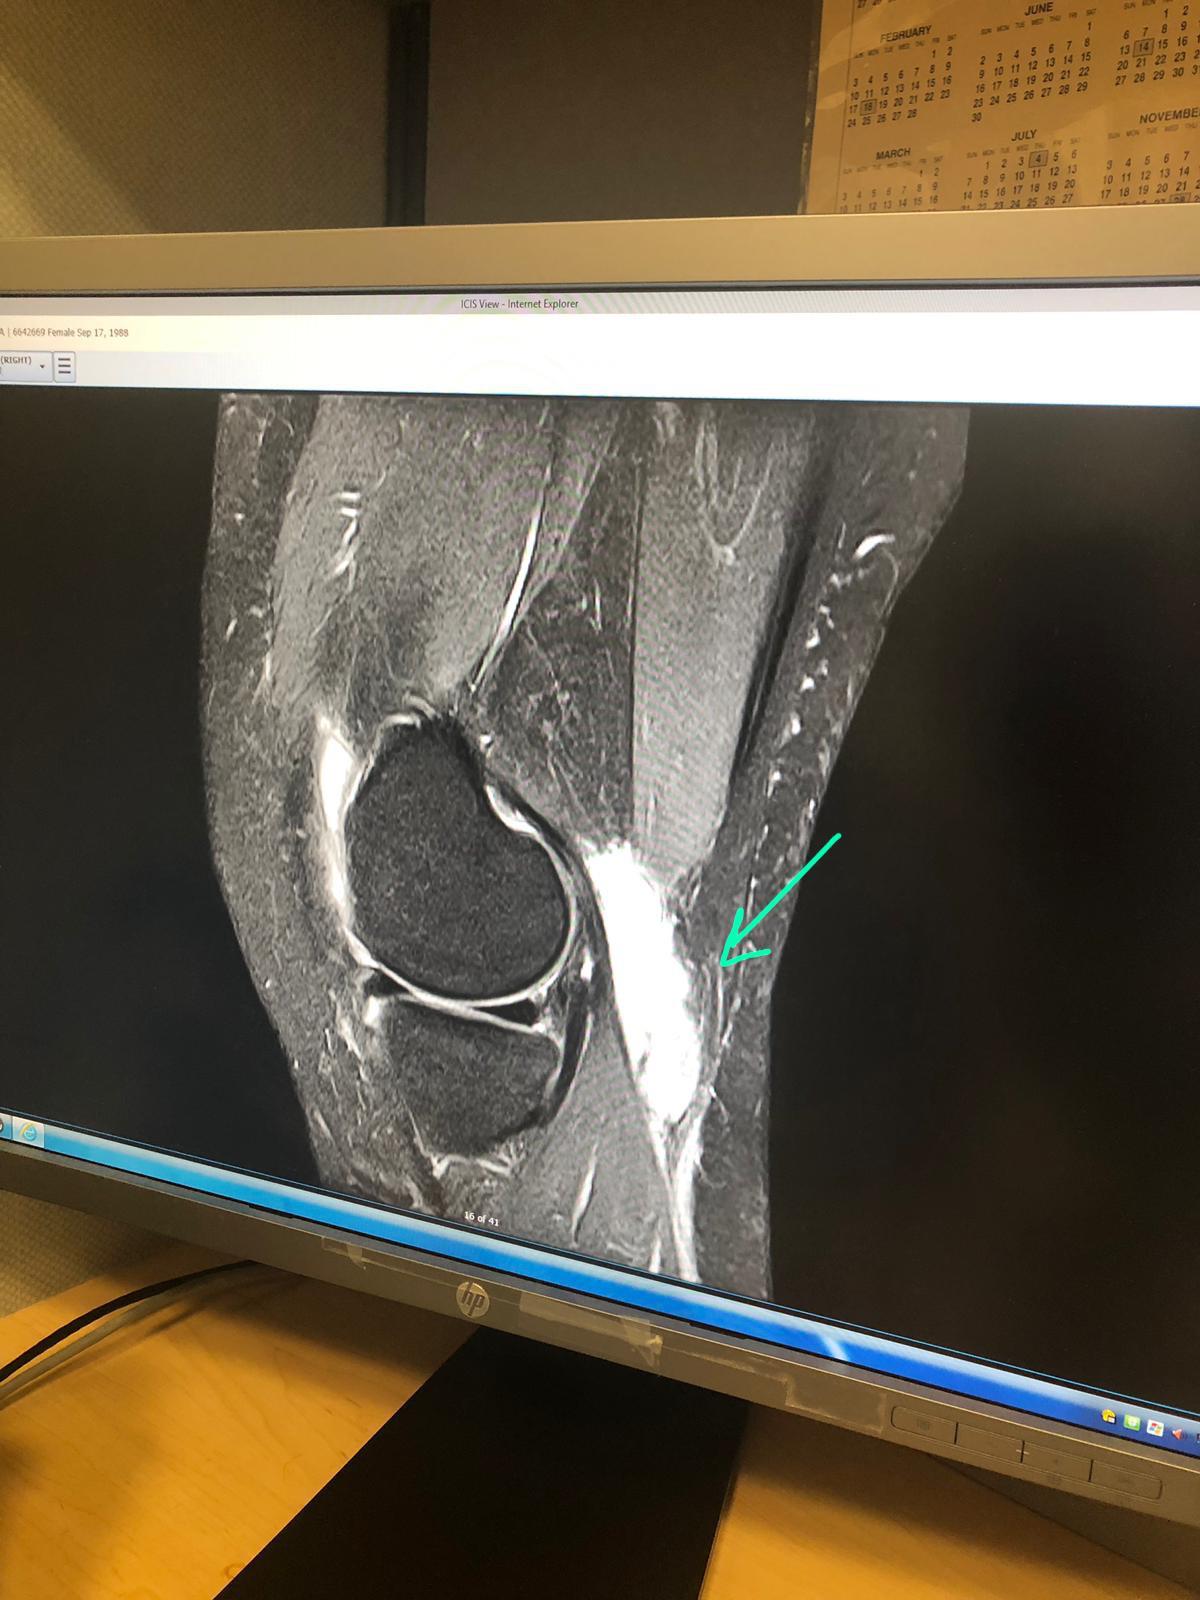

MRI of the Knee showing proximally dissecting ruptured baker cyst Partially Ruptured Baker's Cyst Treatment Learn how to diagnose, treat,. A ruptured baker's cyst causes fluid to leak into your calf, resulting in pain and swelling. It can cause pain, swelling, and complications such as dvt. A ruptured baker's cyst is when the fluid from a cyst behind the knee leaks into the calf. It can rupture and cause pain, swelling and nerve damage in.. Partially Ruptured Baker's Cyst Treatment.